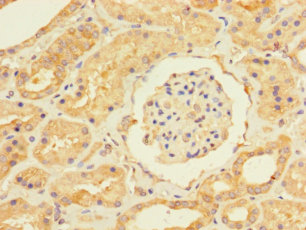

ApplicationELISA, WB, IHC; Recommended dilution: WB:1:1000-1:5000, IHC:1:20-1:200